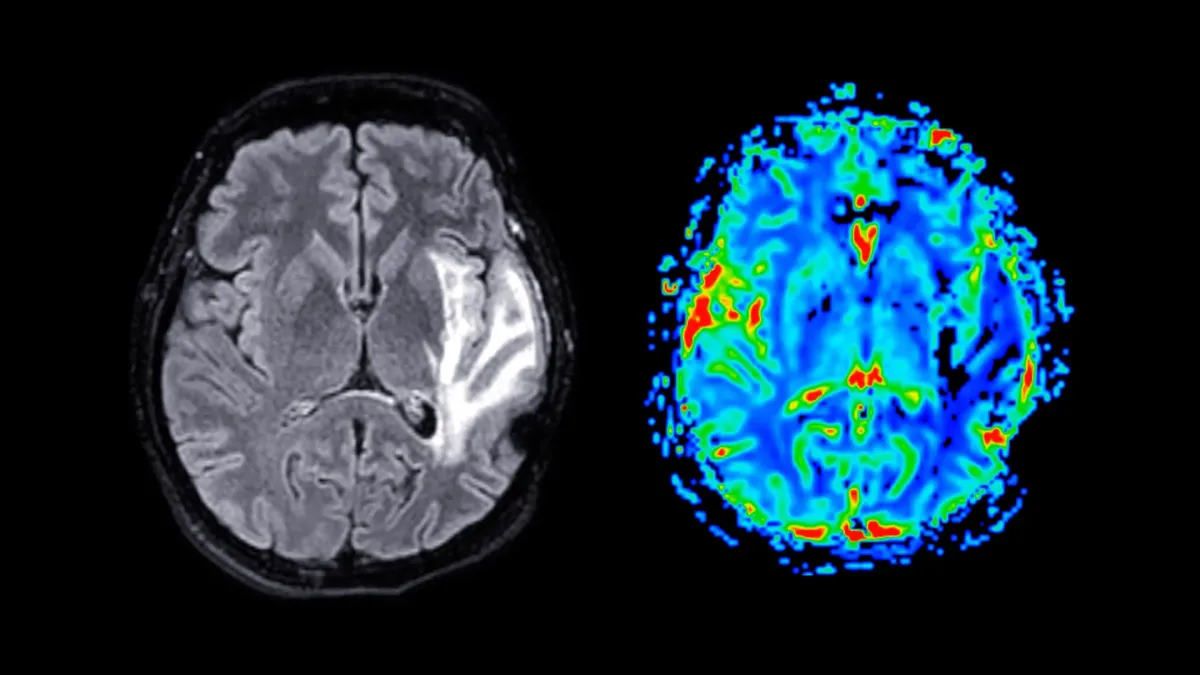

What's Actually Happening in the Brain

The grey matter loss wasn't subtle. The affected brain regions — areas involved in memory storage and emotional control — overlap substantially with those damaged in Alzheimer's disease. This matters because women develop dementia at nearly twice the rate men do, and researchers now suspect menopause could be part of the explanation.